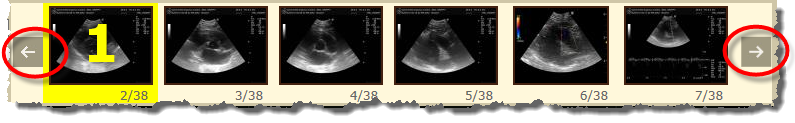

All images for a given study appear in a scrollable thumbnail strip. Clicking on the arrow buttons at either end of the strip will advance through those images (which are all individually numbered e.g. 2/38, 3/38... to indicate image 2 of 38 total in this series, etc.). Selected thumbnail images will have a yellow "1" or "2" overlaid on them to indicate which screen window they appear in. The ability to scroll through these images is particularly useful for US studies where there are a large quantity of images.